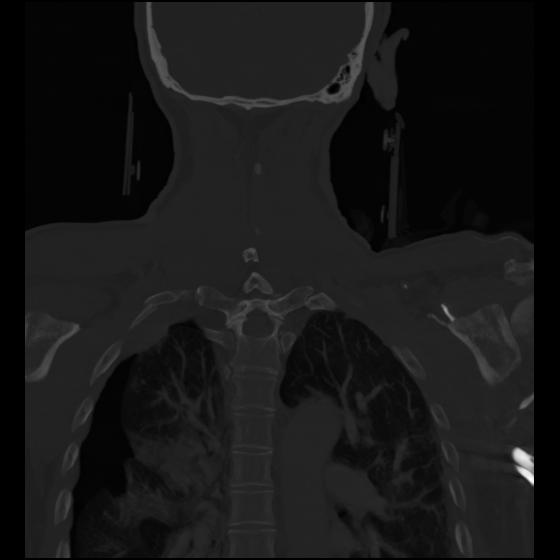

23 ANGIO,CE,Cor-MIP,5.000,ANGIO,Cor-MIP,